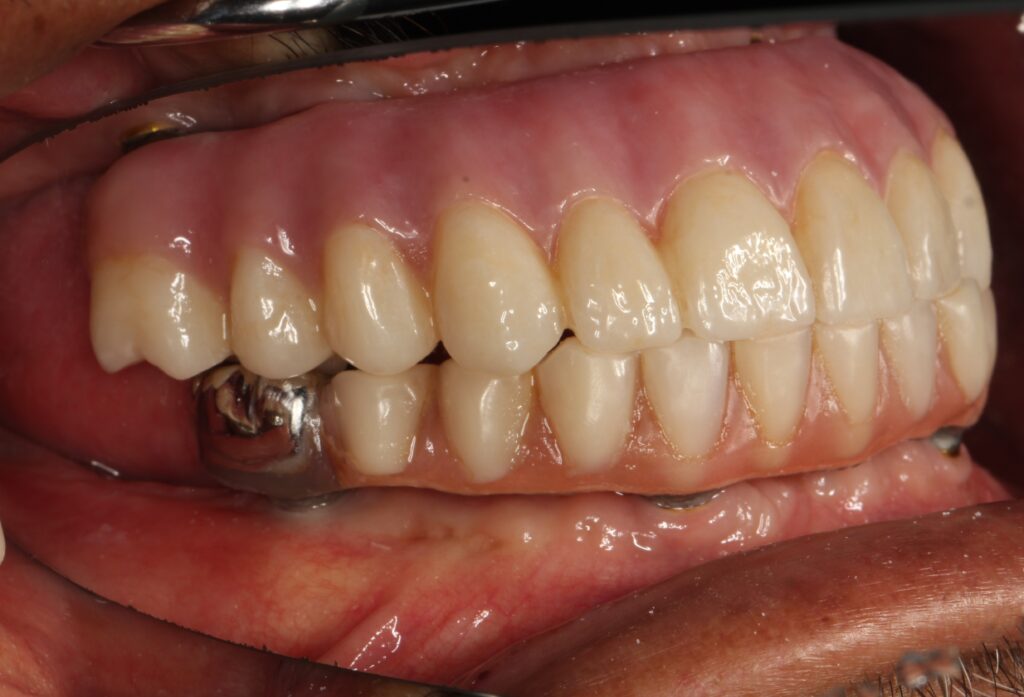

A selection of full arch fixed implant bridge patients after 5 years of wear

Oral Surgeons – Dr Han Choi, Dr Sam Goldsmith, Dr Rajiv Rajpal NSOMS

Prosthodontist – Dr Alan Payne NSOMS/Northland Prosthodontics

Dental technicians – Hosaka Takashi, DT Denture Design, Auckland, CJ Park, Project Dentistry, Auckland and Osteon Medical, Melbourne, Australia.